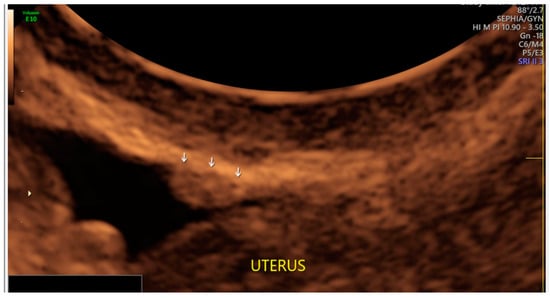

- The presence of hypoechogenic associated tissue (hypoechoic areas surrounding a small cyst area; we called this a “hat”). This tissue does not protrude or invaginate the peritoneal surface.

- The lesion may be convex, protruding from the peritoneal surface into the peritoneal cavity (we called this “bulging”), or it may appear as a concave defect in the peritoneum (we called this a “pocket”).